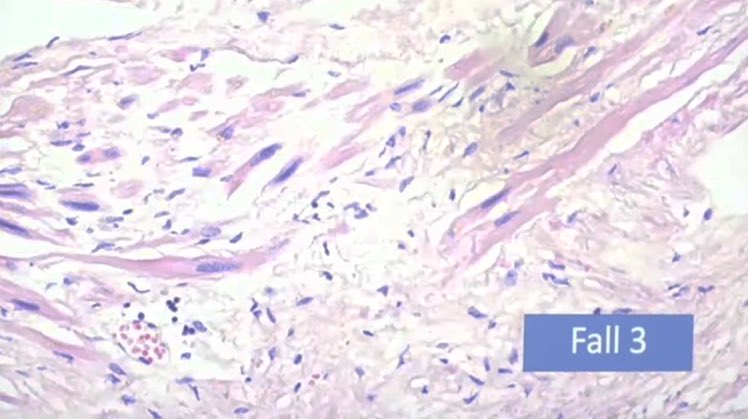

النتائج الرئيسية:

التهاب عضلة القلب اللمفاوي ، التهاب غشاء القلب ، التهاب التامور ، "غلبة الخلايا الليمفاوية" :

⁃نموذجي للعدوى الفيروسية

⁃يصعب التعرف عليها بالميكروسكوب ،

⁃غالبًا ما يُساء تفسيرها من الناحية النسيجية على أنها معدية (الخلايا الحبيبية!). 6️⃣

⁃عادةً ما تكون البؤر صغيرة متعددة ، وبالتالي لا يتم اكتشافها في كثير من الأحيان

⁃التأثير على قدرة الضخ (تحذير: وزن القلب الحرج)

⁃فشل القلب في الجهاز عندما يتأثر نظام التوصيل ؛ "الموت القلبي المفاجئ" ، الاكتشاف بالكاد ممكن (حوالي 15000 قسم)7️⃣